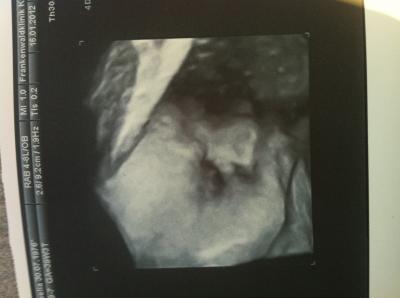

Soooo, bin auch zurück. CTG sah soweit gut aus, Ärztin hatte nix zu beanstanden für die SSW. Allerdings musste aufgrund meines Rückens extra nochmal ein Orthopäde kommen und entscheiden ob ich denn spontan entbinden darf. Er meinte, das es soweit gut aussieht und nix gegen eine Wassergeburt sprechen würde. Im Notfall könnten sie immernoch einen KS machen. Aber eher unwahrscheinlich. *juhu* US war gut. Vince wurde nun auf etwa 2800 g geschätzt, KU 31 cm circa... Nach der Größe hab ich nich gefragt. Ärztin meinte aber das sie mich auf jeden Fall 1 Woche weiterschätzen würde. Tja... Niere sieht nicht gut aus und wenn ich es nicht mehr aushalte, soll ich mit meiner FA reden und in 1,5-2 Wochen wieder kommen, dann probieren wir es mit einem Wehencocktail, da ich bei Luca damals schon so gut und fix darauf angesprochen habe. Ansonsten soll ich am 15.02. dann kommen (also am ET). Soweit also alles supi gelaufen. Hab sogar ein Bild vom Gesicht bekommen *juhuuu*

Bild zu zurück vom Geburtsplanungsgespräch - Forum für Februar - Mamis

Hey das sind ja gute Neuigkeiten. Und das Bild ist ja der Hammer, warum haben die bei euch alle so gute Geräte ich glaub wir Leben hinterm Mond, ist echt schlimm. Naja bald kann ich sie ja live sehen !!! Lg und hoffe das deine Schmerzen nicht jeden Tag so unerträglich sind !!!